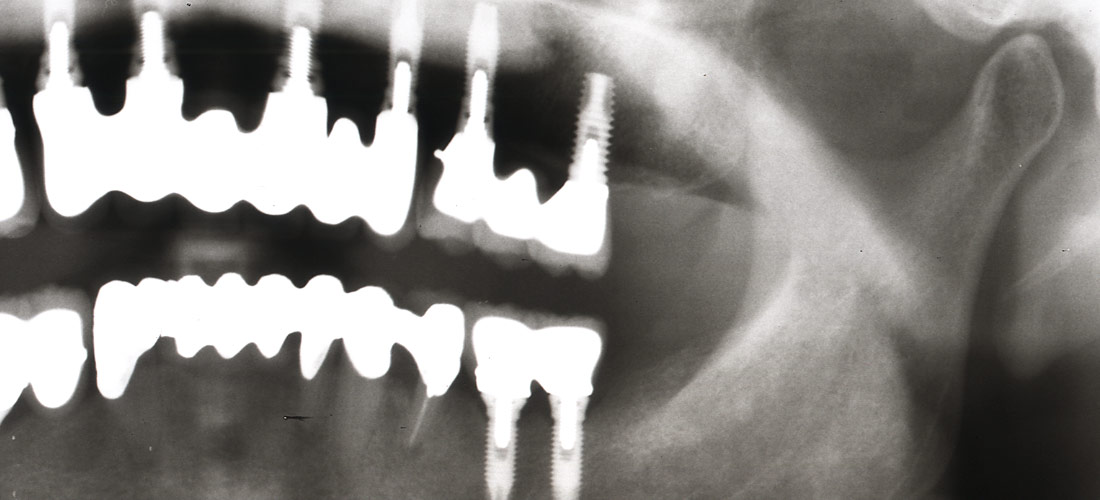

術前

左端の7┓。

レジンのようなものが詰められていますが、応急処置?

大きくはみ出ていて、歯肉にも強い炎症。

術中

詰めてあるものを除去したところ、完全に中の神経の部屋まで虫歯が残っていました。

当院で根管治療開始。

根管充填後

2回の処置で痛みも取れ、綺麗に根管充填できました。

当院で根管治療行うにあたり、隔壁をレジンで作っています。